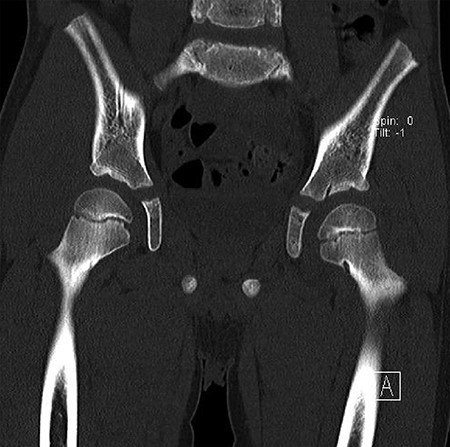

CT hips reported a well-defined lesion seen bilaterally in the neck of femur anterior infero-medial aspect, more prominent on the left side measuring 7 x 3 mm on left side both in coronal (Fig. 3) and axial (Fig. 4) views. On the right side, other lesion measuring 2 x 1 mm (Fig. 5) seen in coronal view. These two lesions are well defined with a sclerotic border with a small cortical defect. The lesion shows fat density. The symmetrical appearance of the lesion combined with the fat density and location suggest the diagnosis of synovial herniation pit. MRI Pelvis revealed minimal left hip joint effusion with loculated fluid seen along the trochanteric bursa with the largest measuring 0.9 x 1.5 cm (Fig. 6, 7).

Showed coronal cut of CT hips demonstrating the synovial pit prominent right side.